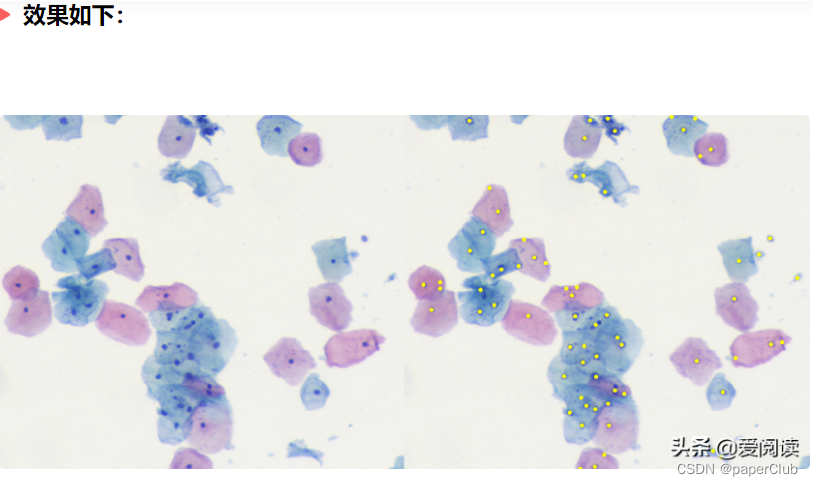

最终细胞核分割定位效果:左边是原图,右边是细胞核行为结果:

例子1:

例子2:

可以看到效果很得不错的。当然这里面还有很大的优化空间。